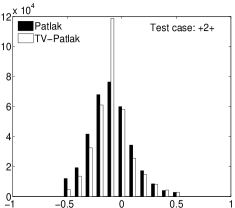

In the images shown in the figures we illustrate the calculated uptake rates of the FDG. Images for the CMRGlc can be obtained by directly scaling . In figure 1 we compare the result of using Patlak and TV-Patlak for estimating the uptake rates with respect to no noise, noise in the input function, Poisson noise in the sinogram, and finally with respect to the case in which the irreversibility assumption is violated but without noise in the sinogram or input data. In each case the histogram of the relative errors is given on the left, the Patlak image in the middle and the TV-Patlak on the right. The different scales in the histograms are due to the total number of results illustrated. When there is no noise (triples and ) the histogram illustrates results over all voxels but only one simulation, while for the noisy simulations the results are for all voxels over all realizations of the noise. The TV-Patlak images are more homogeneous in all cases and the relative errors are smaller. The figures clearly show the improvements of employing the TV-Patlak method as compared to using Patlak independently for each voxel. This is confirmed in figure 2 in which images with noise in the sinogram, positive and different noise levels in the input function are shown.